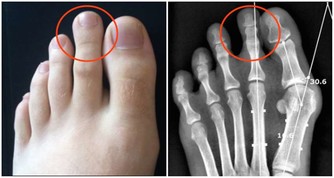

如果你睡眠很好、堅持鍛煉、吃得健康,並且壓力有限,但仍然總是很累,那麼最好去看看醫生。

因為下列疾病可以導致過度疲勞:貧血、焦慮症、慢性疲勞綜合症、抑鬱、糖尿病、食物不耐受、心髒病、營養素缺乏症、甲狀腺功能減退症、懷孕、尿路感染等。